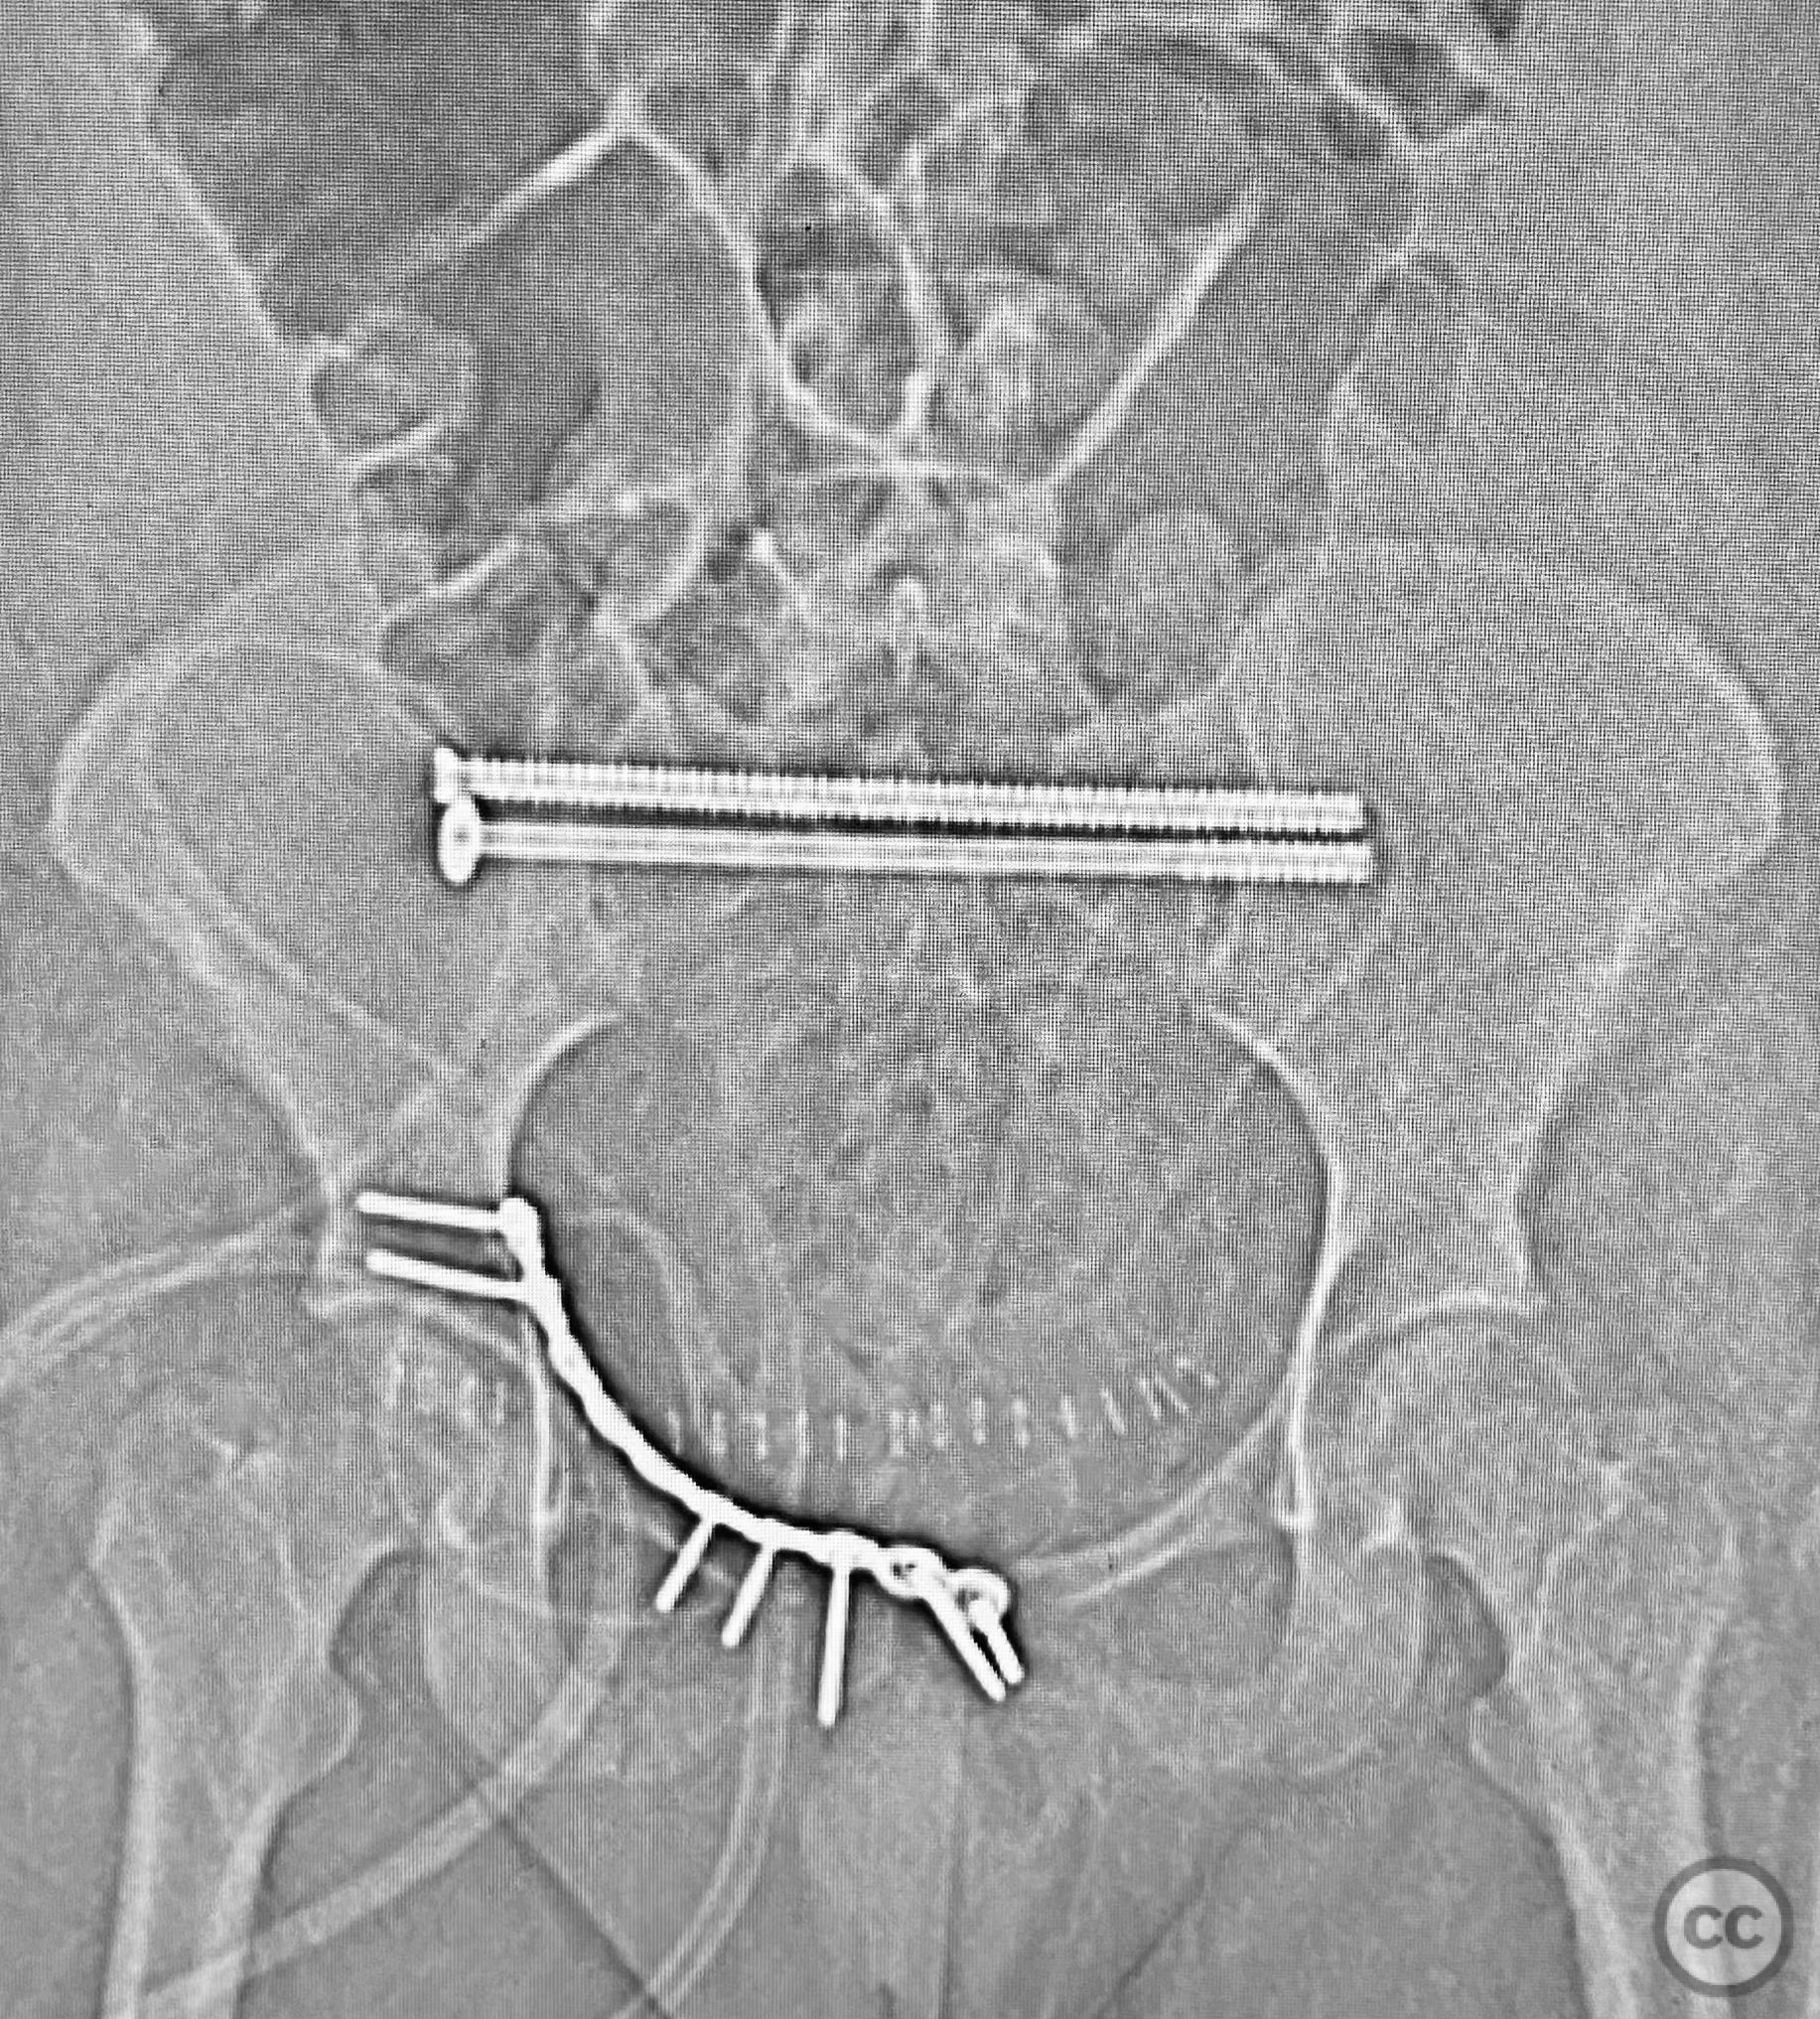

Clinical and radiological findings:  A young adult female sustained a high-energy pelvic injury following a motorcycle crash. She was hemodynamically stable on presentation, with normal neurovascular examination and no evidence of genitourinary, vaginal, or rectal injury. She reported pain localized to both anterior and posterior pelvic regions. Initial plain radiographs (with and without pelvic binder) demonstrated multiple anterior ring fractures and dislocations. The binder images obscured the full extent of injury. Further intraoperative fluoroscopic imaging (AP, inlet, and with lower extremities in "lotus" position) revealed bilateral sacroiliac (SI) joint disruptions (right greater than left), bilateral superior/inferior pubic ramus fractures (right greater than left), and symphyseal diastasis. Notably, the right pubic ramus demonstrated excessive curvature, complicating potential percutaneous screw fixation. AO/OTA classification: 61-C1.3 (bilateral complete disruption of the posterior arch with associated anterior ring injury). Young-Burgess classification: APC III.

Planning remarks:  The preoperative plan included open reduction and internal fixation (ORIF) of the displaced right pubic ramus fracture and symphyseal diastasis via an anterior approach, with acceptance of indirect closed reduction of the SI joints. Percutaneous trans-sacral screw fixation was planned for stabilization of the posterior pelvic ring. Due to the complex curvature of the right ramus, straight screw fixation was deemed unsuitable.

Intraoperative fluoroscopy with AP and inlet views, as well as dynamic positioning of the lower extremities, was critical in fully delineating the extent of injury, which had been underestimated on preoperative imaging due to binder application. The excessively curved morphology of the right pubic ramus precluded safe or effective straight screw fixation; therefore, ORIF with a contoured plate was performed using intrapelvic exposure for optimal fit and stability. Indirect closed reduction of the SI joints was accepted, followed by percutaneous trans-sacral screw fixation under fluoroscopic guidance. This case highlights the necessity of thorough intraoperative assessment for occult or underestimated injury patterns in complex pelvic trauma, particularly when initial imaging is performed with a pelvic binder in situ.